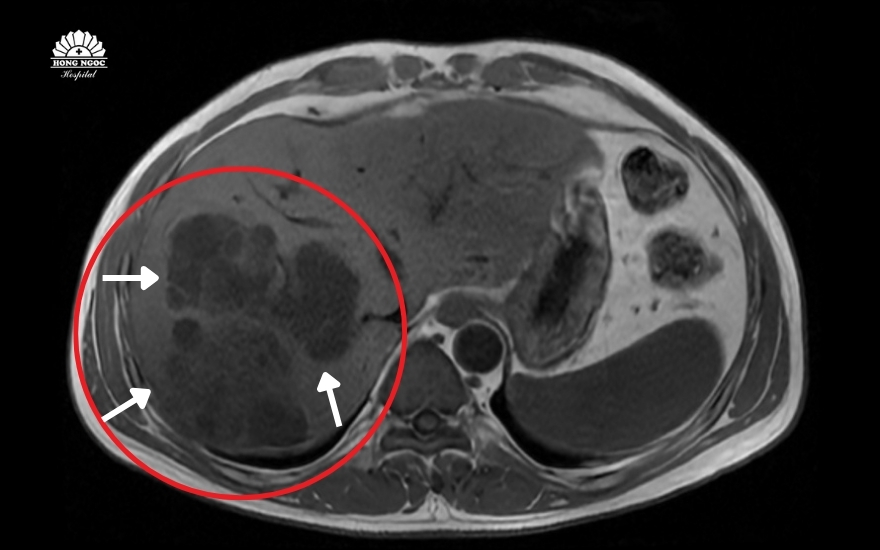

Đồng thời, kết quả siêu âm và chụp MRI ổ bụng cũng cho thấy nhu mô gan phải vùng hạ phân thùy VII – VIII, xuất hiện một ổ tổn thương áp xe kích thước lớn lên tới 109 x 102 x 74mm và những ổ nhỏ. Đáng lo ngại hơn, đây không phải một ổ mủ đơn thuần mà cấu trúc chứa nhiều vách và có vỏ dày, tạo thành các chùm nang sát vỏ gan nguy cơ vỡ.

Ổ áp xe kích thước lớn, có nhiều vách ngăn tạo thành các chùm nang